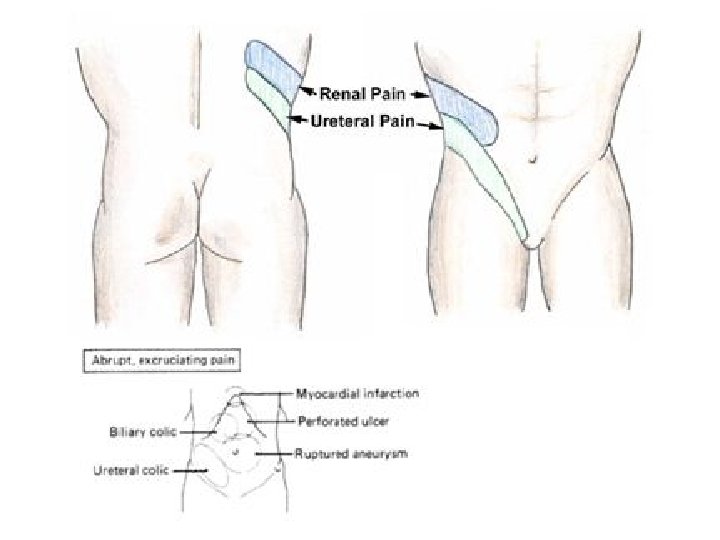

• DIAGNOZA DIFERENCIALE: - Appendisiti (ne fazen fillestare) - Pankreatiti - Patologjite renale dexter: infeksion apo kalkul ne ureter: *Anamneza *Ekzaminime laboratorik (urine) *Ekzaminime radiologjike te aparatit urinar